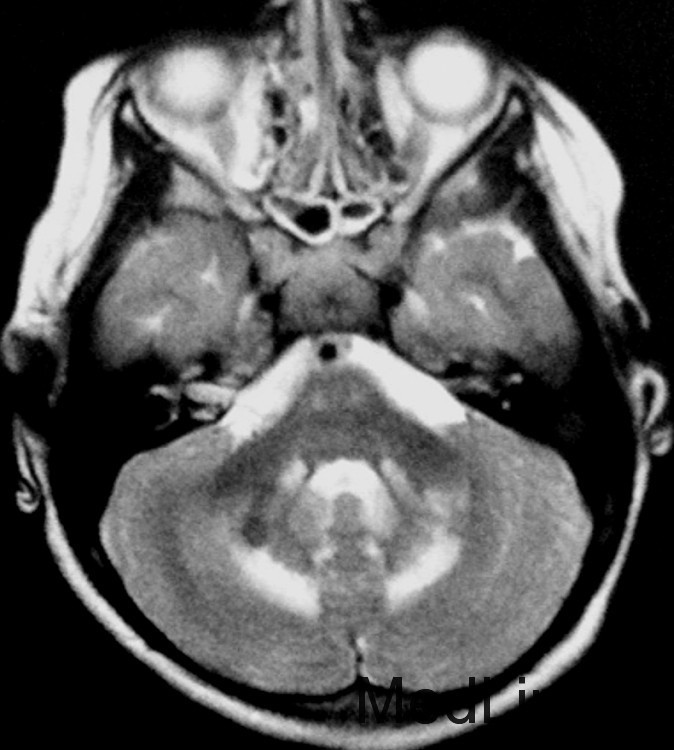

神经科查体显示肌僵直,腱反射亢进,双侧病理征阳性,轻度的小脑共济失调,振动觉及本体觉异常。CSF正常。 T2WI显示幕上及幕下白质T2高信号。内囊后肢、脑干皮质脊髓束、小脑中脚均受累。脊髓T2WI可见皮质脊髓侧束T2高信号。

简称LBSL,是一种常染色体隐形遗传病,一般为DARS2基因突变引起。临床主要表现为儿童期及成年期缓慢进展的肌僵直、小脑性共济失调、振动觉及本体感觉异常。认知可轻度受累。意识、神经症状恶化可由轻度的头部损伤引起。诊断要点:特征性的临床症状及MRI异常。证实需做基因检测。MRS和CSF可见乳酸轻度增高,但没有特异性。MRI是诊断的很好标准。(AJNR-clinical correlation)